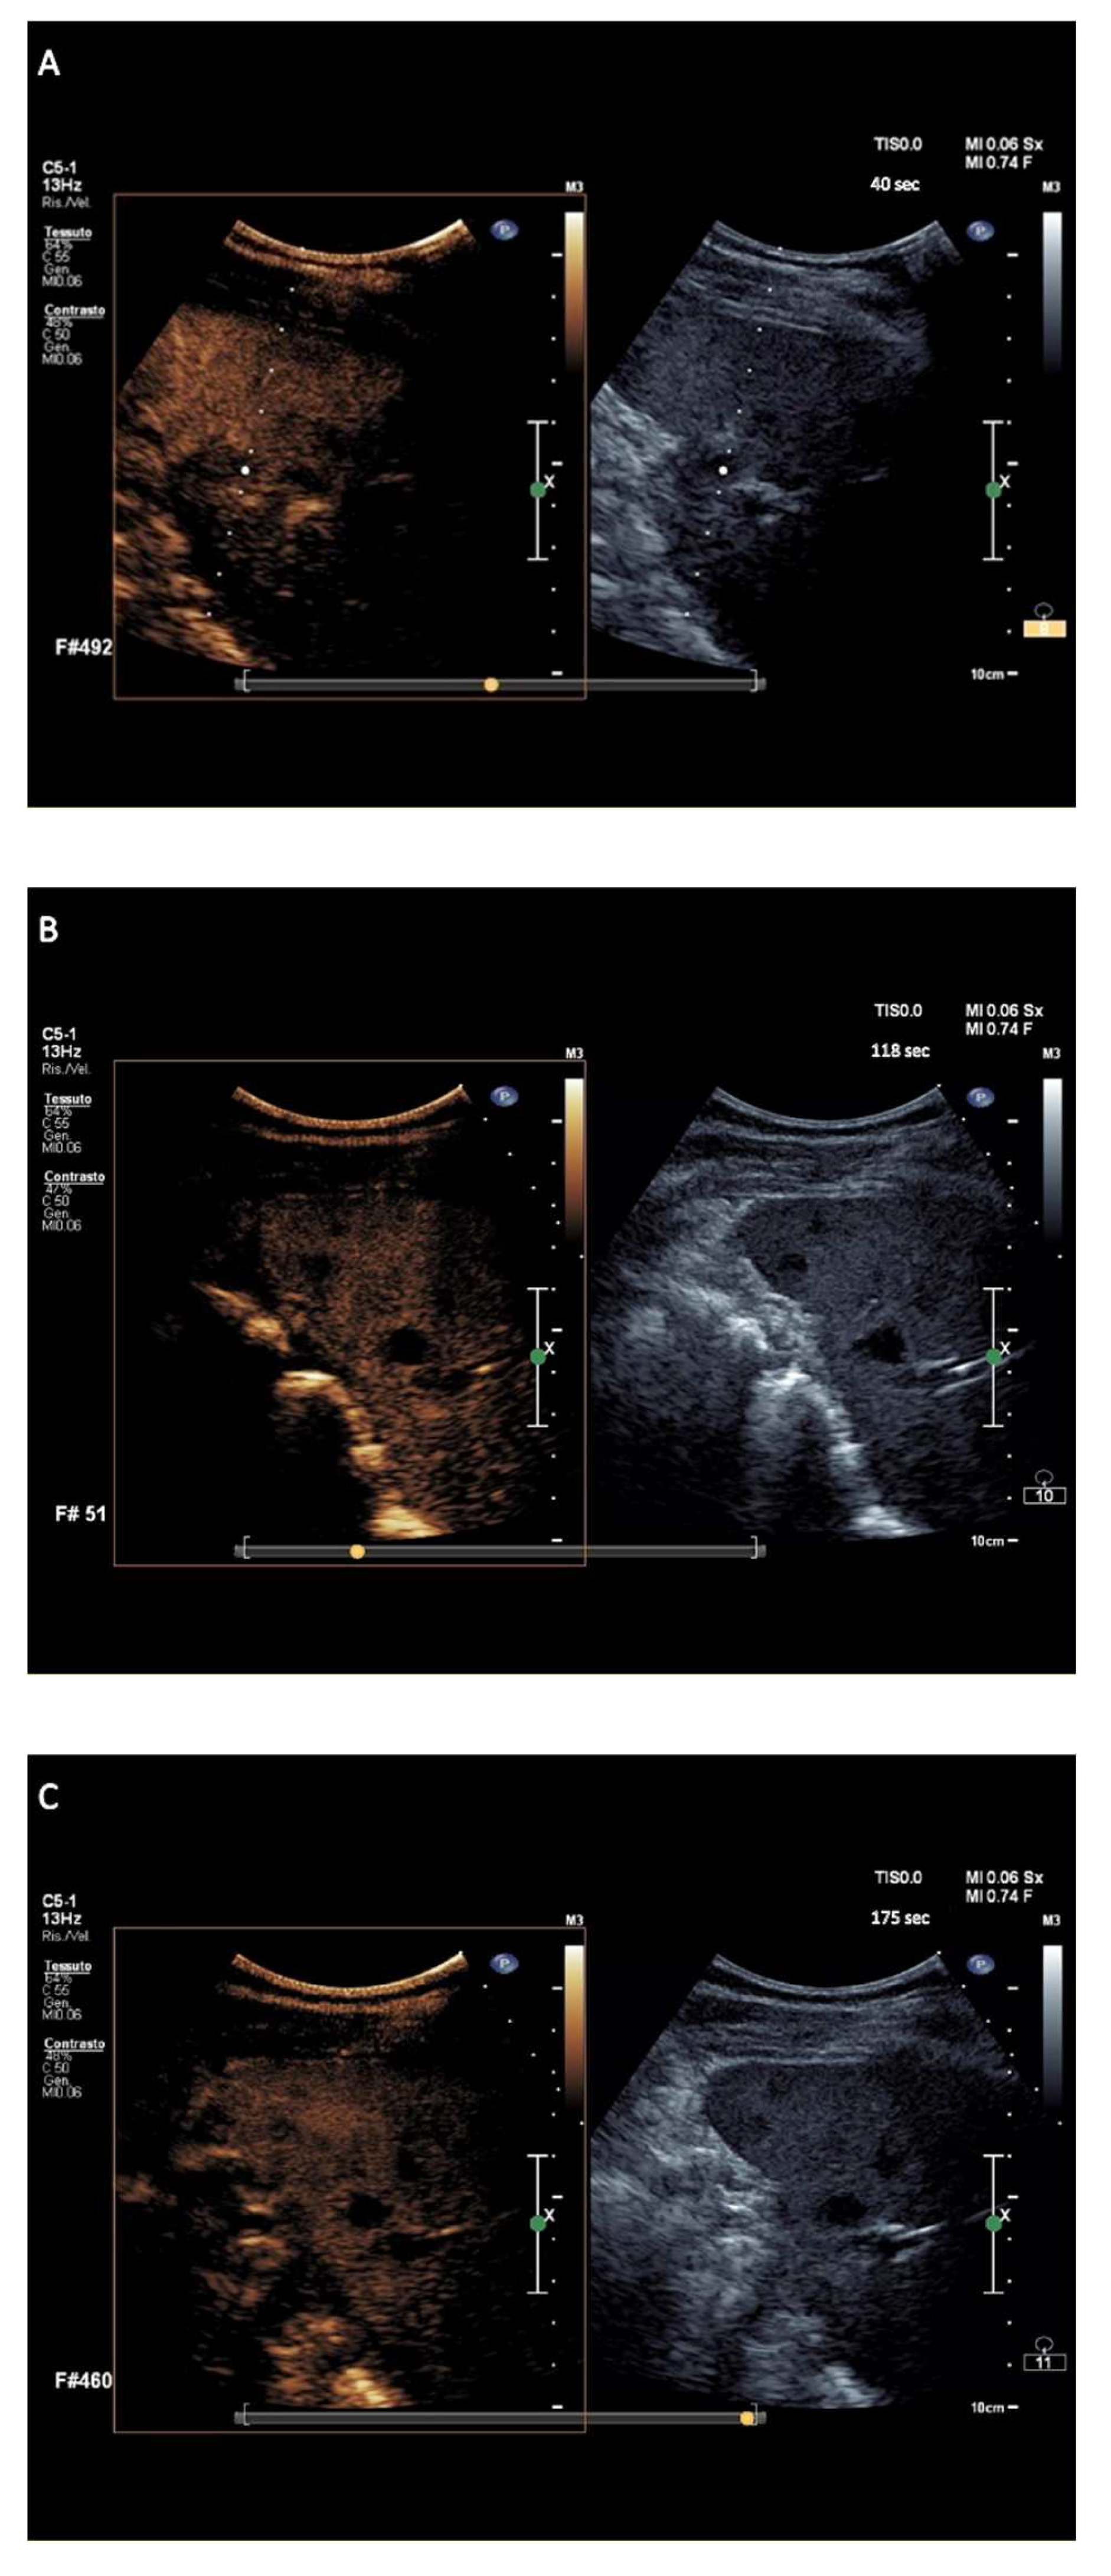

C-HL nodules showed isoenhancement in the arterial phase followed by early wash-out onset appearance and marked in degree between 90 and 110 s following contrast agent injection, in a total of 57/60 (95%) nodules (Figure 3). The 60 nodules of exploratory c-HL-DC had the onset of wash-out occurring at a median of 43 s (range 25–48 s) with a median of marked wash-out of 100 s (range 92–120 s).

Figure 3.

Major features of CEUS according to the exploratory diagnostic criteria. (A–C) showing classic Hodgkin lymphoma nodule with discretely marked wash-out, at 92 s from contrast agent injection.

Finally, i-NHL nodules displayed isoenhancement in the arterial phase followed by wash-out appearance that was early in onset and marked in degree between >110 and ≤120 s following contrast agent injection, in a total of 10/12 (83%) nodules (Figure 4). The wash-out onset for the 12 nodules of exploratory i-NHL-DC occurred at a median of 44 s (range 41–59 s) with a median of marked wash-out of 114.5 s (range 101–120 s).

Figure 4.

Major features of CEUS according to the exploratory diagnostic criteria. (A–C) showing indolent non-Hodgkin lymphoma nodules with sufficiently marked wash-out, at 118 s from contrast agent injection.

The hallmark sign of lymphomatous nodular infiltration of spleen consisted of arterial phase isoehnacement followed by early (<60 s) and marked (≤120 s) wash-out appearance of sulfur exafluoride microbubbles. This finding validated the effectiveness of temporal CEUS enhancement and wash-out criteria to establish the diagnosis of involvement by lymphoma. The three principal clinical subtypes of lymphomas analyzed in the study, i.e., a-NHL, c-HL, and i-NHL, were differentiated on the basis of the degree of wash-out intensity (from contrast injection) of nodules. The totality of a-NHL nodules was categorized according to the typical wash-out appearance of very marked degree, i.e., within <90 s following contrast agent injection (Figure 2A–C) resulting in a PPV of 100% (95% CI, 97–100%). Most c-HL nodules tended to be categorized in wash-out appearance of discretely marked degree, i.e., between 90 and 110 s following contrast agent injection (Figure 3A–C), with PPV of 96.6% (95% CI, 88.3–99.6%). Most i-NHL nodules tended to segregate in a diagnostic category characterized by a wash-out appearance that was sufficiently marked in degree, i.e., between >110 and ≤120 s following contrast agent injection (Figure 4A–C), with PPV of 77% (95% CI, 46.2–95%).